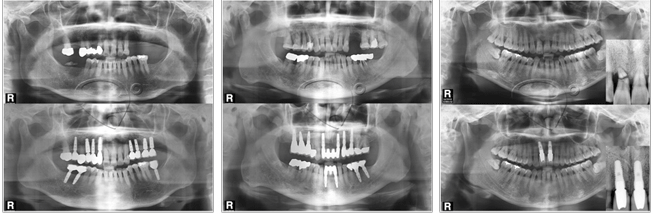

- 58对于不喜欢牙科的患者好消息! 睡眠种植牙是对于种植牙手术害怕,痛症,机械噪音等这种许多原因不能接受手术的患者开始的手术方式。睡觉的状态上没有痛症,害怕时接受种植牙手术的方式。跟全身麻醉不同有意识的状态上进行,非常平安的精神状态比较安全的手术方式后遗症也很少。最近普遍化的手术。 睡眠种植牙是通过静脉注射假睡眠状态上一些麻醉手术。这种睡眠种植牙手术是进行时几乎没有手术中的记忆,非常舒服所以可以说镇静麻醉。